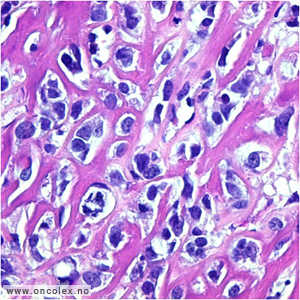

Osteosarkom er det vanligste sarkomet i ben. Mikroskopisk ses malignt utseende celler som produserer benvev eller osteoid. Det finnes mange subtyper. Klassifikasjon baseres på lokalisasjon i knokkelen og på kliniske, radiologiske og mikroskopiske funn.

Histologisk bilde av osteoblastisk osteosarkom. |

Klassisk osteosarkom

Klassisk osteosarkom ses hos unge i alderen 10–30 og sitter i metafysen i lange rørknokler, typisk rundt kneet og øverst i overarmen. Tumor viser malignt utseende celler som produserer osteoid og ben med forkalkninger. Det kan i tillegg ofte påvises områder med kondroblastisk og/eller fibroblastisk utseende. Dersom man ikke får representativ biopsi kan man feilaktig stille diagnosen kondrosarkom eller fibrosarkom på et slikt materiale.